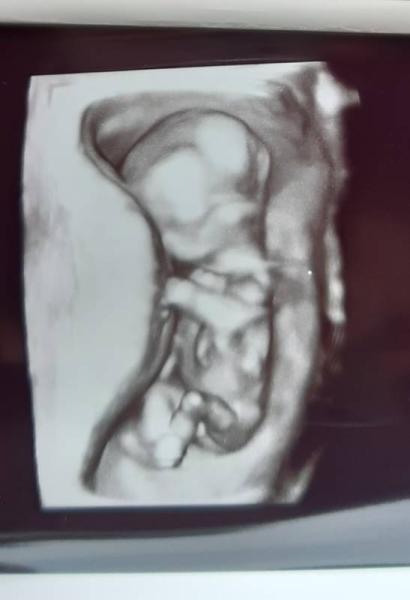

Hallo ihr Lieben Wir kommen gerade von der NFM. Mein Mann und meine "Große" waren auch dabei. Es war ein schöner Termin, keine Auffälligkeiten. Ich weiß, eine Garantie gibt es nie aber das ist der erste Schritt Nun ja, das Kleine ist 7 cm groß, aber ansonsten in allem sogar noch schmaler als meine Süße damals. Dachte gar nicht, dass das noch geht Mit ziemlich hoher Wahrscheinlichkeit bekommen wir diesmal einen kleinen Jungen Der Schniepel war sehr gut zu erkennen. Aber offiziell geht eben in der 13. Woche noch nicht. Wir freuen uns sehr!!!!

Bild zu NFM und Outing - Forum für Januar - Mamis

Glückwunsch zum (inoffiziellen ) Jungen und, dass alles gut ist Ein wundervolles Bild habt ihr da heute bekommen Ich hoffe auf ein Outing zum nächsten Termin in der 20.SSW beim Organscreening

Herzlichen Glückwunsch zum ... Das Bild ist echt toll